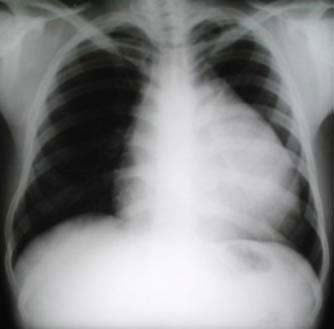

un paciente joven, con un gran tumor del mediastino anterosuperior de rápido

crecimiento, correlacionando su tamaño entre la radiografía

del tórax y los hallazgos tomográficos realizado 15 días

después, y las condiciones físicas al momento de su intervención,

con gran dificultad respiratoria.